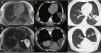

Our patient was a 39-year-old man who underwent echocardiography because of clinical palpitations. A mass was visualized in the left lateral-apical region and tentatively diagnosed as a pericardial cyst. Magnetic resonance imaging (MRI) was performed showing a fluid collection in the left fissure with a portion in the cardiophrenic angle (Fig. 1A and B).

A–F) Migrating pleuropericardial cyst: A) MRI T1-enhanced axial image showing hypointense lesion (asterisk) in the left fissure. B) MRI T2-enhanced axial image showing hyperintense lesion (asterisk) in left fissure extending to pericardium (arrow). C) CT axial image obtained in supine position revealing a lesion of fluid density (asterisk). D) CT axial image obtained in prone position showing a lesion of fluid density (asterisk) with anterior shift compared to in the supine position. E) CT axial image obtained in supine position in lung window showing lesion (asterisk) in.

We decided to expand the study with computed tomography (CT) focusing on the lesion, collecting images in supine and prone decubitus. A fluid collection was observed in the left fissure when the patient was supine, in the paracardiac region when he was in right lateral decubitus, and in the anterior region in prone decubitus (Fig. 1C and F). Part of the collection remained in the cardiophrenic angle in all scans, suggesting a diagnosis of migratory pleuropericardial cyst.